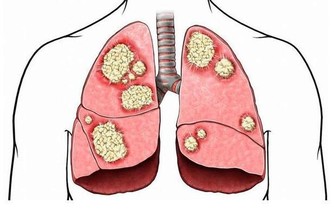

如果我們體內的尿酸過高,體內就會出現結晶,腎小管可能因此被堵塞,造成無尿的現象。如果經常這樣,我們體內的毒素不能排出,就會積累在身體內,久而久之,就會威脅身體健康。